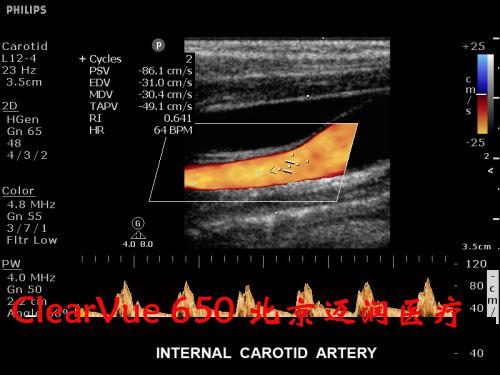

飛利浦ClearVue?CV650彩超

飛利浦ClearVue CV650(HD11XE升級版)是集成了飛利浦多項先進超聲技術(shù)的全身應(yīng)用型實時三維彩色超聲診斷系統(tǒng),采用了飛利浦最新的“元設(shè)計”理念。在原始信號的采集上,CV650飛利浦專利的超聲探頭微信號處理技術(shù)(雙A探頭技術(shù)),保證了零損耗寫真級實時數(shù)據(jù)采集,呈現(xiàn)更真實的圖像信息,可以大大減少臨床上的誤診與漏診的發(fā)生率。

該設(shè)備凝聚了前沿的圖像處理技術(shù)和實用的臨床解決方案,ClearVue CV650適用于腹部、婦產(chǎn)科、小器官、兒科、心臟、外周血管、泌尿系、肌肉骨骼以及術(shù)中檢查和介入診斷治療。

飛利浦ClearVue 650超聲系統(tǒng)臨床高清圖片